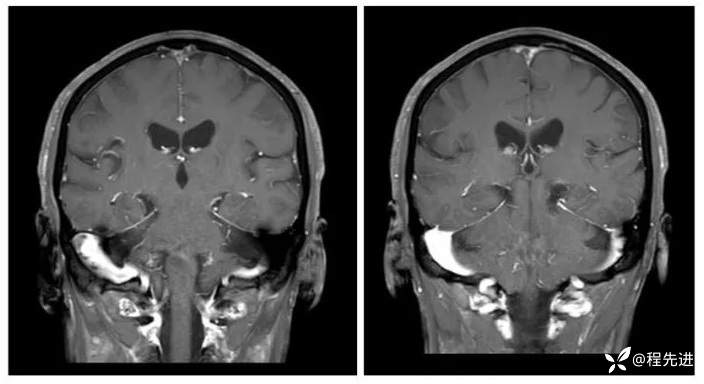

MRI平扫+增强:

T1增强冠状位:

FLAIR增强: